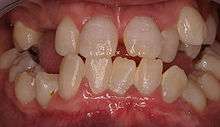

Dentin dysplasia is a genetic disorder of teeth, commonly exhibiting an autosomal dominant inheritance. It is characterized by presence of normal enamel but atypical dentin with abnormal pulpal morphology. There are two types. Type I is the radicular type, and type II is the coronal type. In the radicular type, the roots of teeth are shorter than normal and the pulp chamber may be nearly gone. The pulp chamber is sometimes described as having a "crescent shaped" appearance. In the coronal type, the pulps are enlarged and are described as having a "thistle tube" appearance, in permanent dentition. In the deciduous dentition, coronal dentin dysplasia bears a resemblance to Dentinogenesis Imperfecta type II.